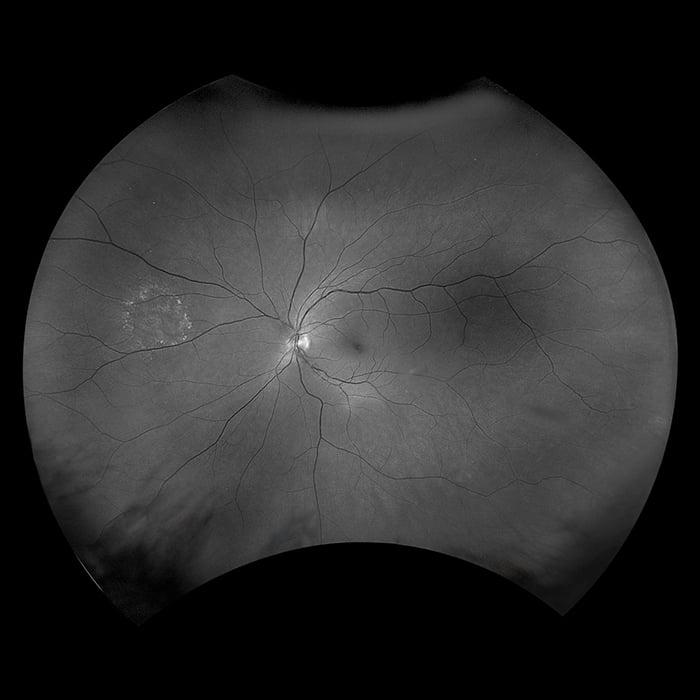

Optos introduced ultra-widefield (UWF™) retinal imaging to enable eyecare professionals to discover, diagnose, document and treat ocular pathology that may first present in the periphery - pathology which may go undetected using traditional examination techniques and equipment. Our UWF, high-resolution retinal imaging devices each image more than 80% or 200˚ of the retina in a single shot. Our complete list of ultra-widefield retinal imaging devices is below.

California was developed for medical imaging and is a standard for retinal screening programs. California is available in multiple models with multiple imaging modality options. California produces a 200°, single shot retinal image of unrivaled clarity in less than ½ second and is changing the management of diseases including Geographic Atrophy, Diabetic Retinopathy, AMD, and Uveitis.

Daytona produces a 200° single shot optomap retinal image of unrivaled clarity in less than ½ second. This fast, easy, patient-friendly, ultra-widefield imaging technology was designed for healthy eye screening and has been shown to improve practice flow and patient engagement.